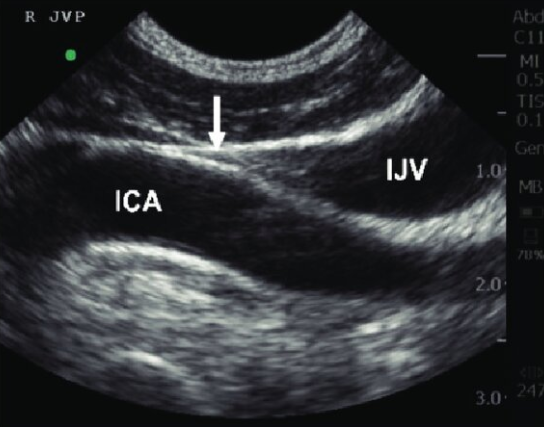

Extending my gratitude to @ross_prager @arntfield for letting me come to London and see the great things you’re doing with point of care ultrasound (POCUS).

#pocus #hemodynamics #vexus